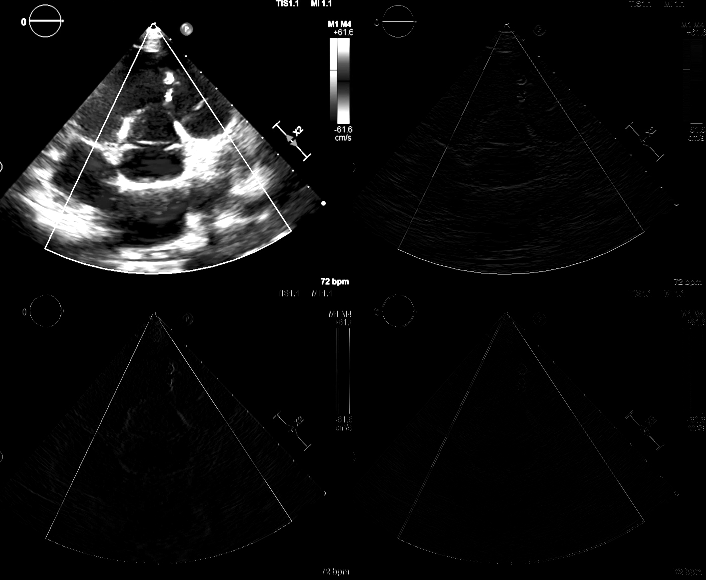

*下圖為小波轉換後的結果